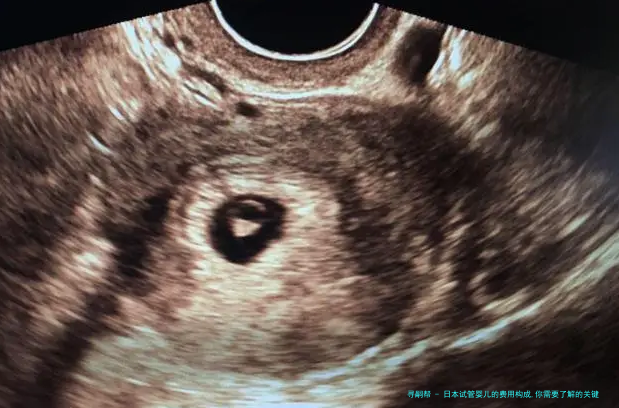

日本试管婴儿技术在全世界声誉卓著,吸引了很多夫妻前往求医。然而,认识日本试管婴儿的费用构成是每位求医生必须留意的关键点。下列是关于日本试管婴儿费用构成的细致说明。

3. 手术费用:试管婴儿手术囊括、胚胎培育和胚胎移植等环节。手术费用约为3万至5万元。

4. 试验室费用:胚胎培养和基因筛查等实践室操作须要高昂的成本。这部分费用一般来说在2万至4万元。